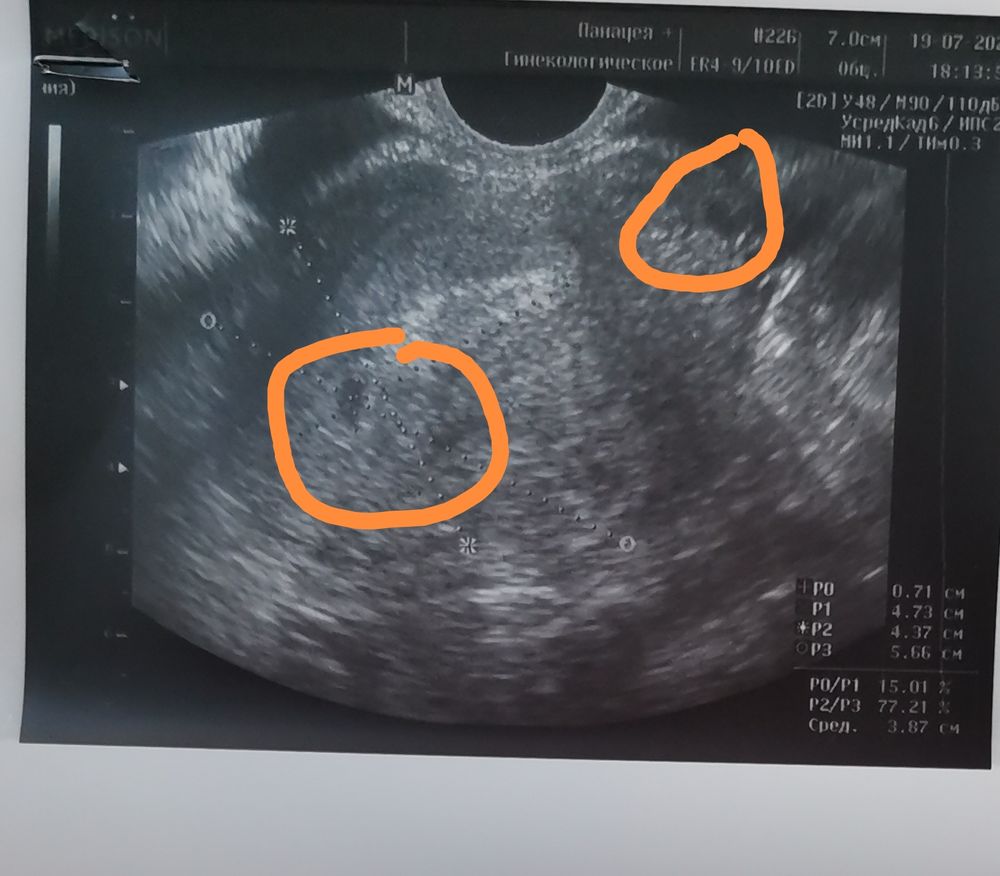

Всем привет. Недавно узнала что б. С последней даты м 4-5 недель, по узи 2-3 недели. Врач сказала что похоже на 1 плодное яйцо, но на снимки вижу два затемнения.точно ли одно яйцо?

Там отмечена матка линиями этими, вот внутри матки одно плодное яйцо. А второе затемнение вне матки, это скорее или шейка матки(там всегда есть затемнения) или же яичник с фолликулами. Но больше похоже на шейку матки